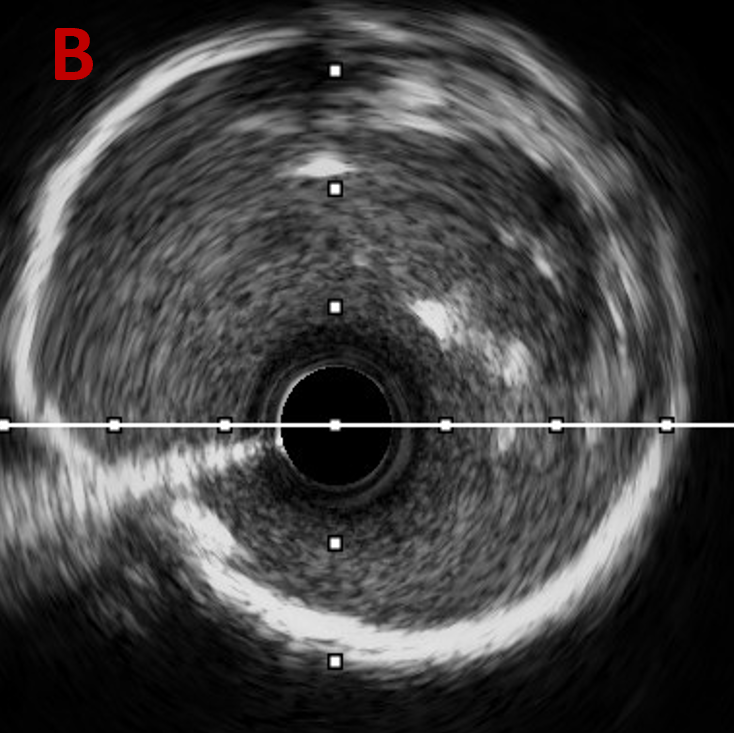

复查IVUS可见:LAD多处环形钙化,原支架贴壁不良,支架远端导丝走形在支架外,IVUS指导下重新调整导丝进入支架

经后扩复查IVUS

-

LAD中远段支架贴壁良好,LAD开口显示有明显支架贴壁不良

LAD近端EEM直径4.74mm,送入4.5*15 NC进行后扩